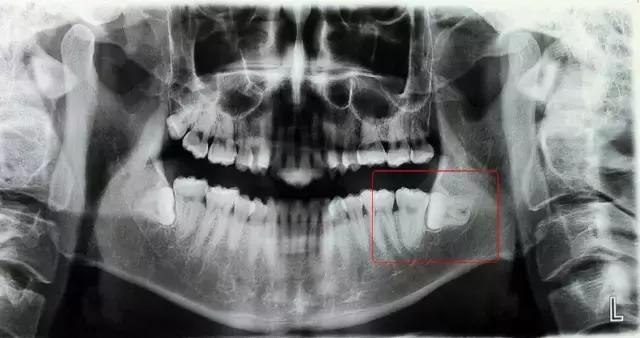

小今医生: 不奇怪,智齿一般都会长歪,你这个是完全横着长的, 叫高位水平阻生,属于相对比较难拔的。拔除需要把牙龈切开,去少量骨,是个小手术哟~

阻生齿可以粗略分为以下几类:垂直阻生、近中阻生、水平阻生;高位、中位、低位;拔除难度一般成递进关系。